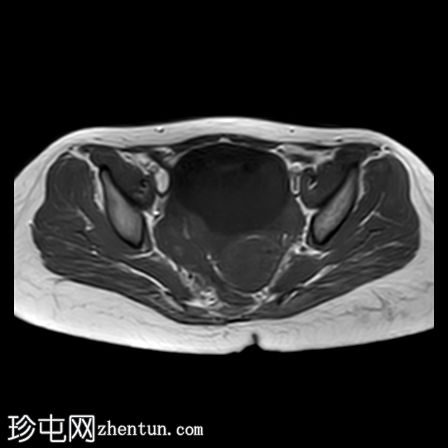

冠状位

T1加权像

右侧卵巢增大,卵泡呈周边排列。

附件血管蒂扭转(漩涡征)。

右侧附件旁可见一较大的、边界清晰的盆腔囊性病变,向右倾斜,提示为卵巢旁囊肿。

本病例展示了卵巢扭转的典型影像学特征,包括卵巢增大、卵泡呈周边移位、卵巢向内侧偏移以及特征性的漩涡征。

在这种情况下,较大的卵巢旁囊肿被认为是发生卵巢扭转的高危因素。如果卵巢旁囊肿较大(>5厘米)或活动度较大,其重量/活动度增加会牵拉附件,导致卵巢和输卵管发生扭转。